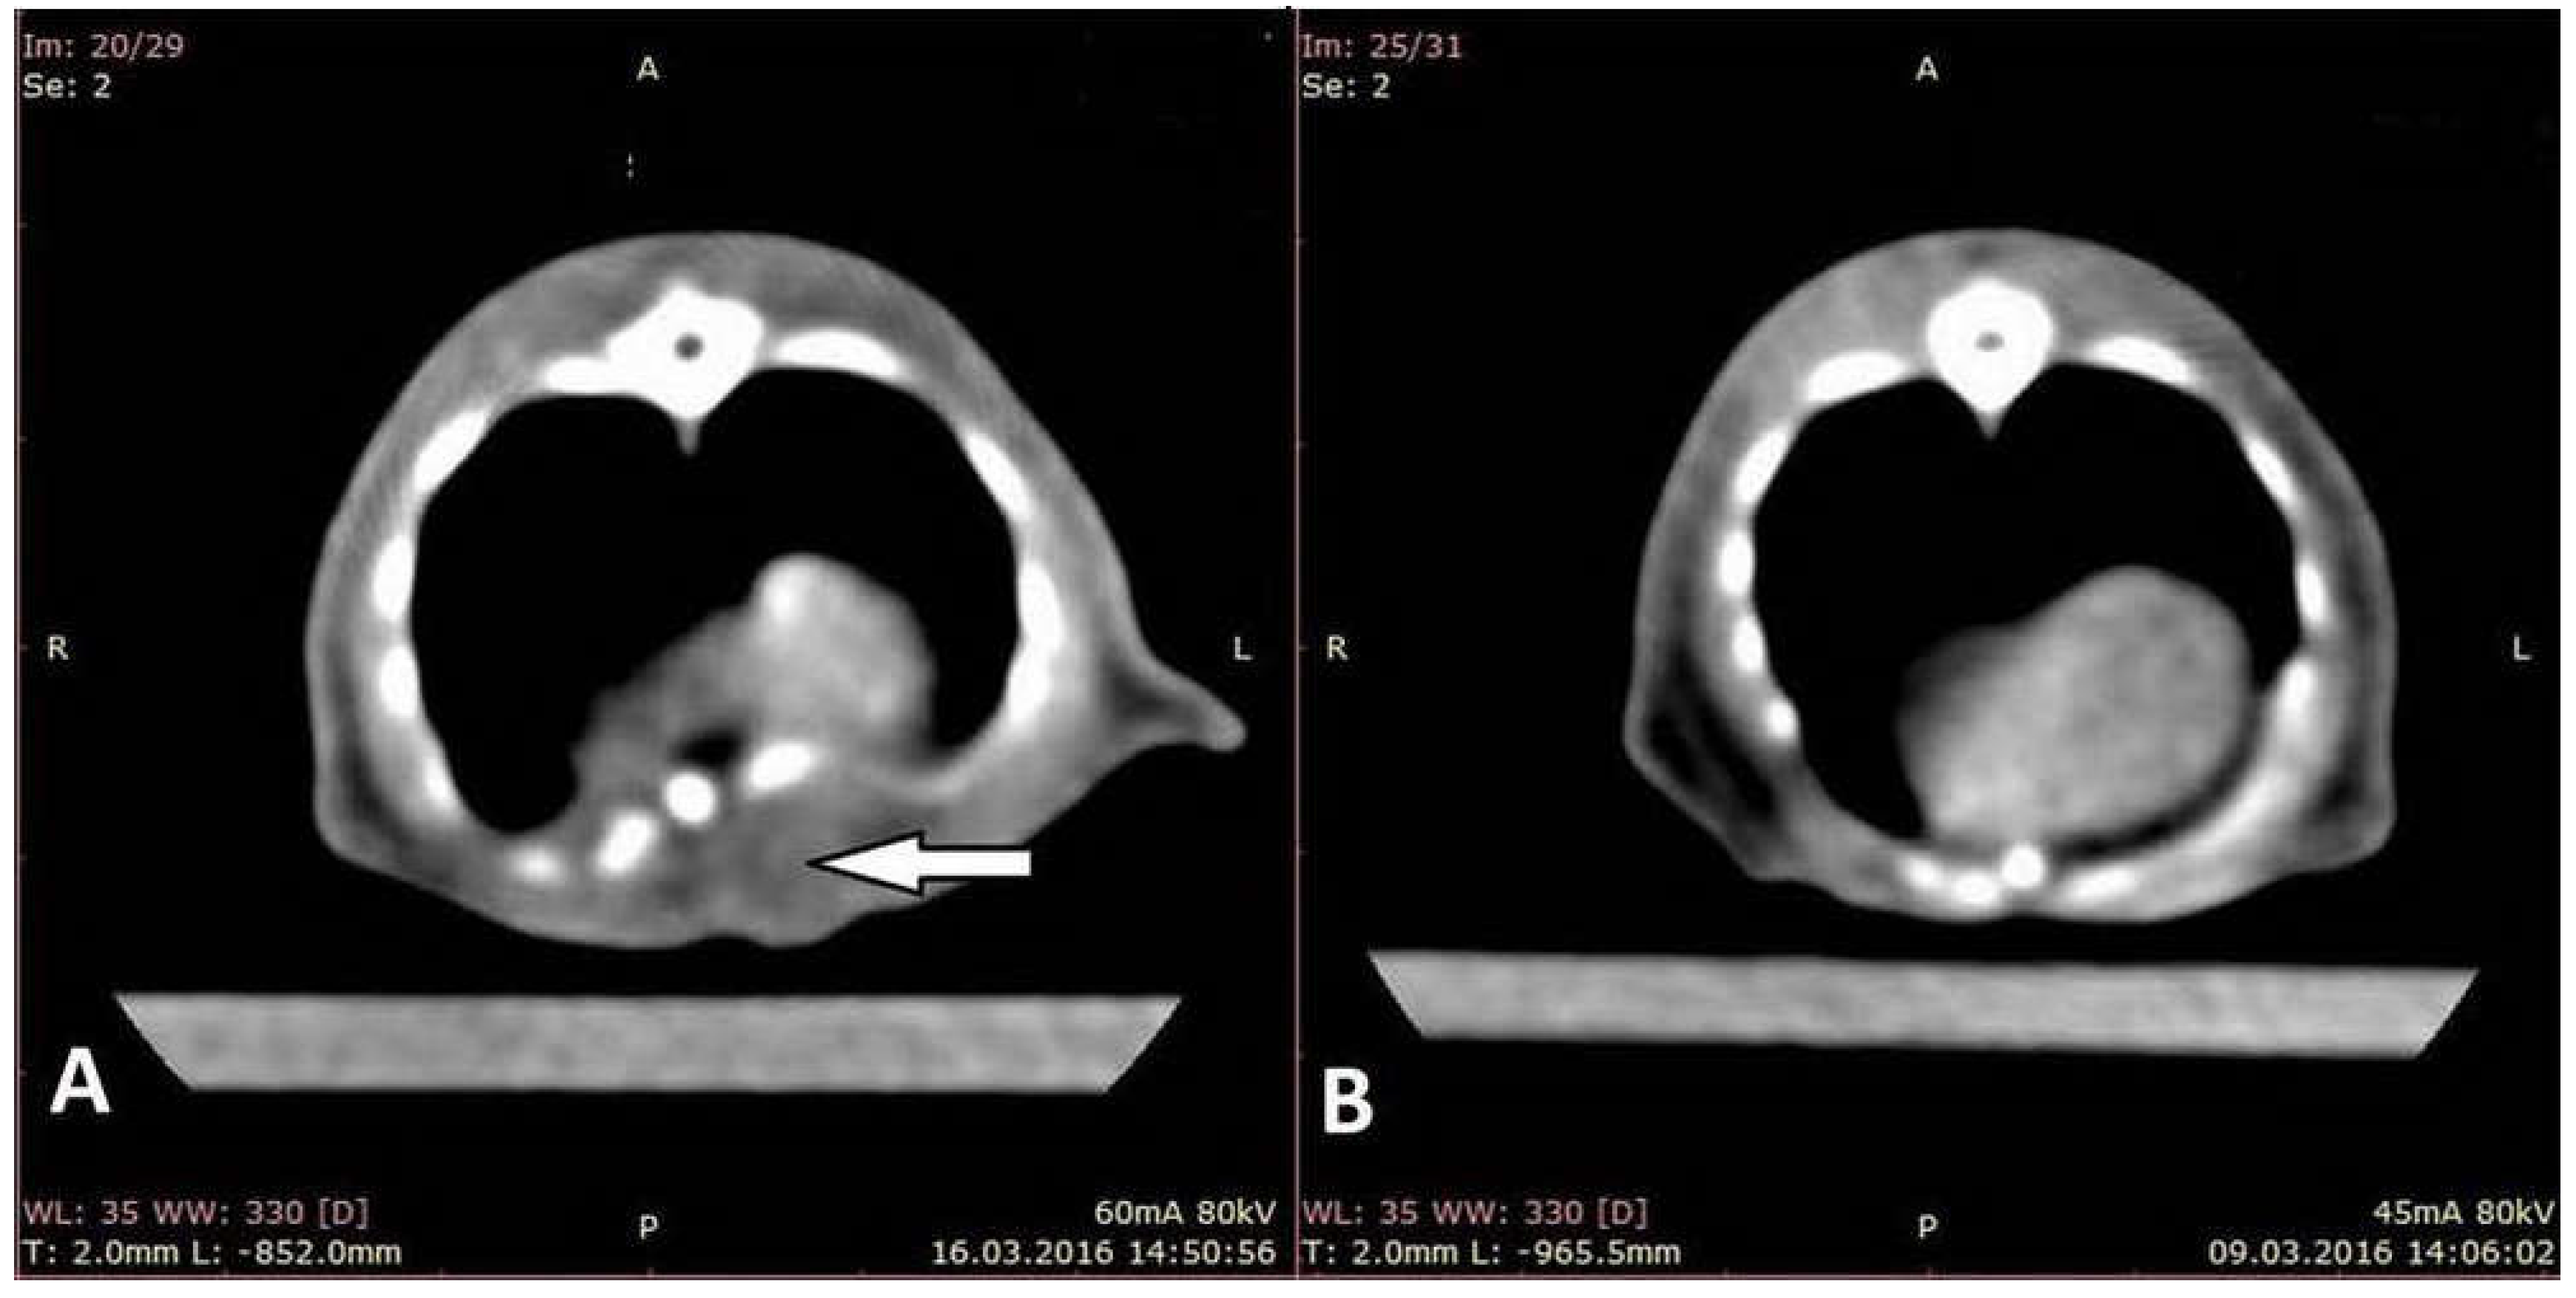

3.1. Assessment on CT Images